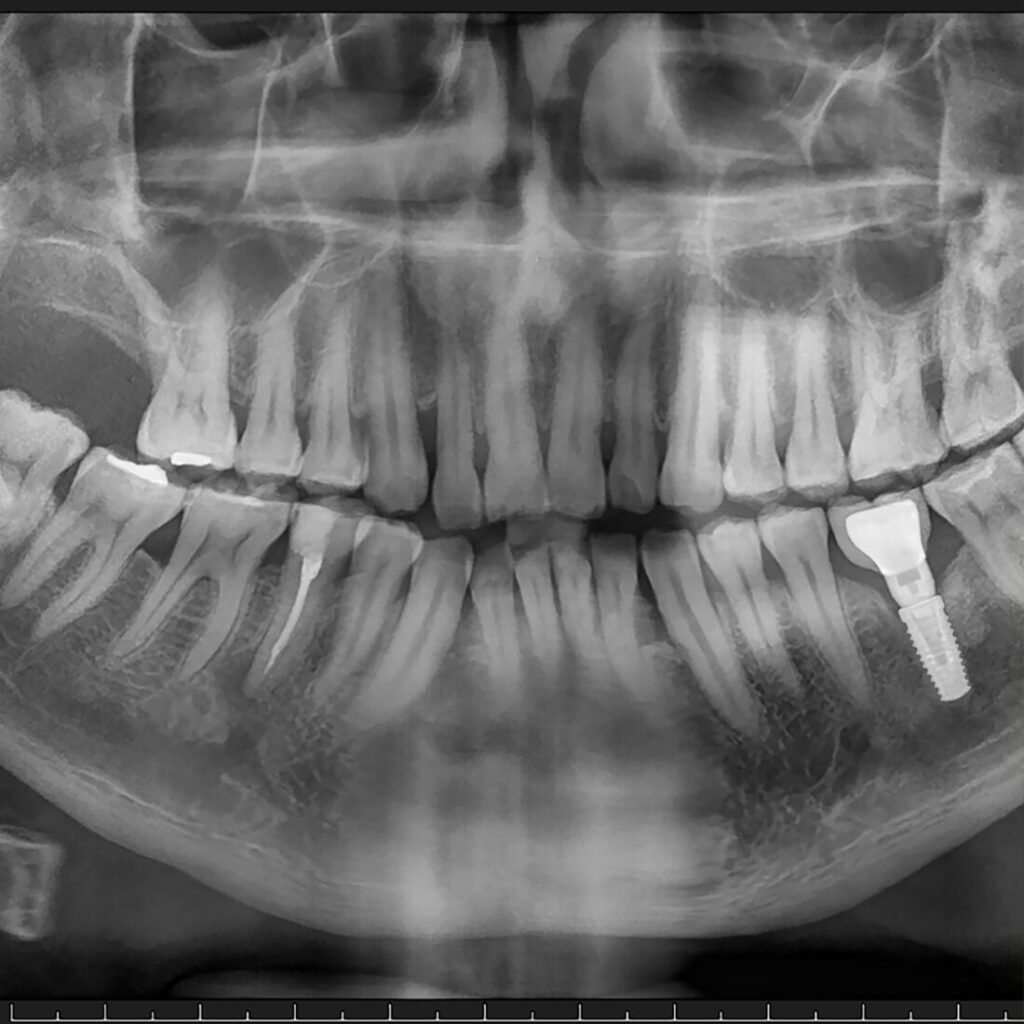

- postępująca utrata kości widoczna w RTG,

- postępująca utrata kości widoczna w RTG.